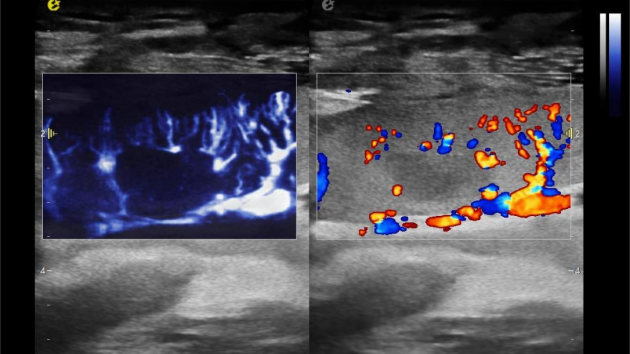

1) 基于OmniSound?平面波超快速平台,超声信号采集帧频提高了200倍(25000Hz)。

2) 可检测20-50μm级细小血管低速血流信号,能看清头发丝1/2粗细的微血管;

3) 通过血管指数(VI)定量评估局部血管密度,以定量化数据实时监测血流灌注情况,预判肾功能恢复情况;

超微视血流显像显示肾脏五级血管

肾脏的灌注评估,RI/VI量化数据

超微视血流显像评估肾移植术后灌注情况

这一项无创、无辐射操作简便且无需造影剂的黑科技,相当于用"高速摄像机"记录血液细胞的运动轨迹,让血管并发症"无处遁形。